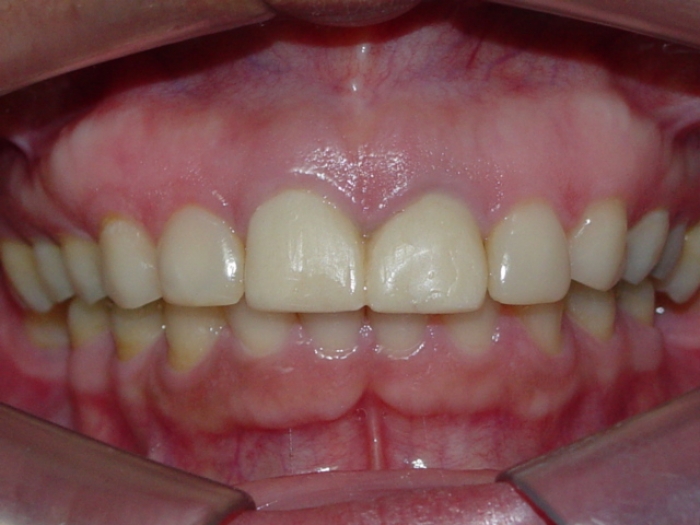

Prótese fixa em porcelana sobre implante Cone Morse

Sorriso final, do caso terminado em outubro de 2011

Sorriso Final, Controle em 2013